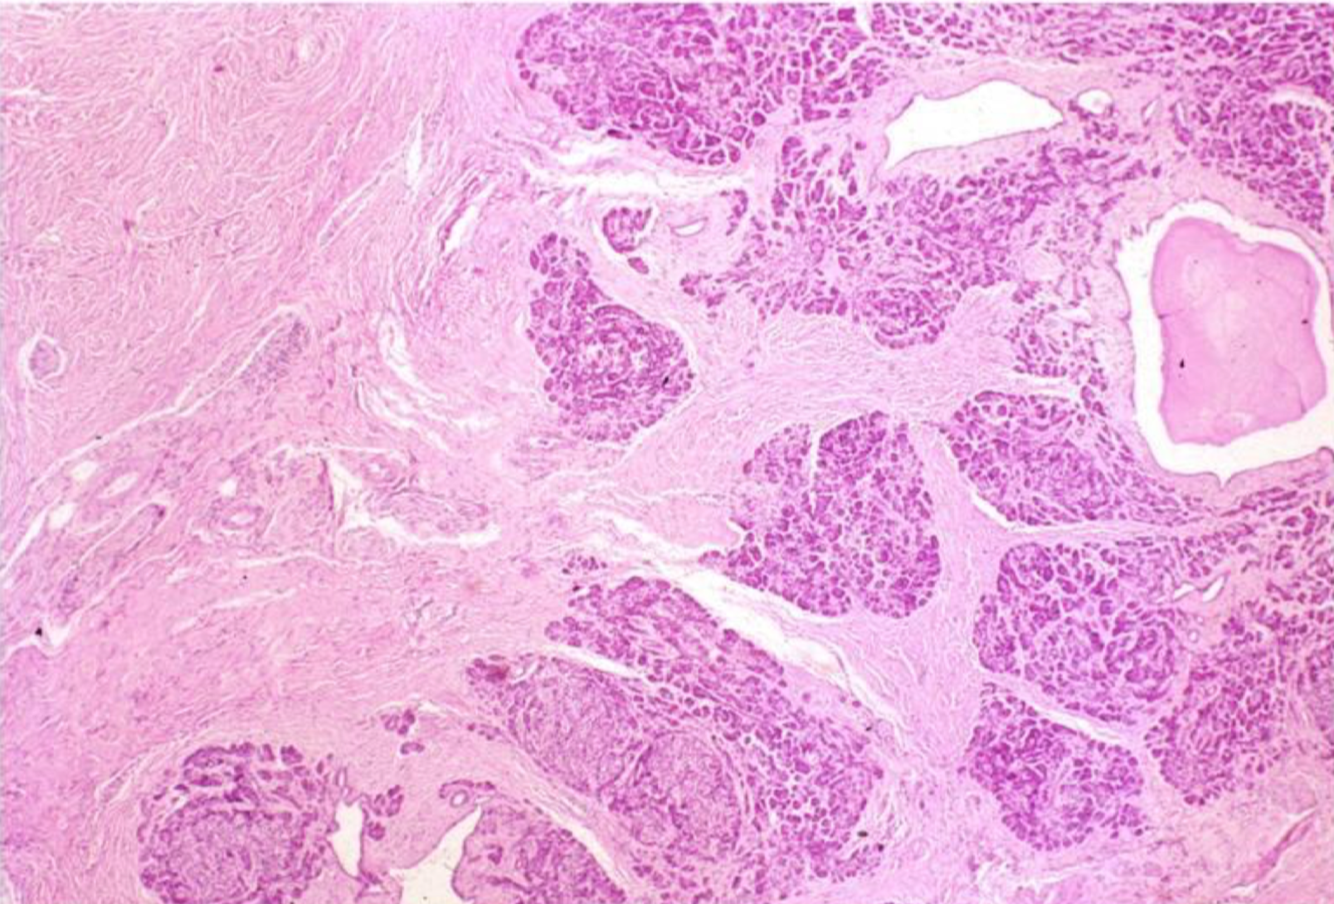

This is a pancreas. Do you think this is a case or acute, or chronic pancreatitis?

Chronic, there is a ton of scarring!